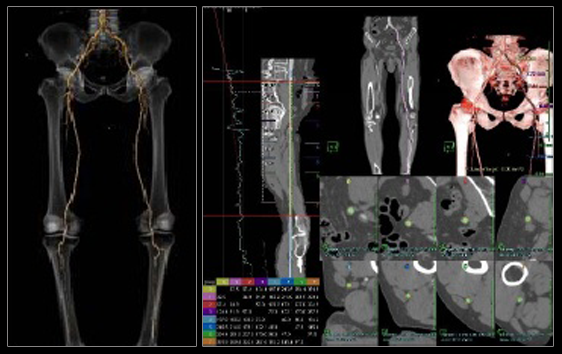

采用了最先进的驱动技术,极大的提高了信号的传输效率,确保进行快速的扫描。 机架采用标准几何设计,射线扇形角小。 机架上横断位,矢状位,冠状位三个方向定位灯,确保定位的快速准确。 采用呵护患者的先进设计,机架开口径达 750mm。